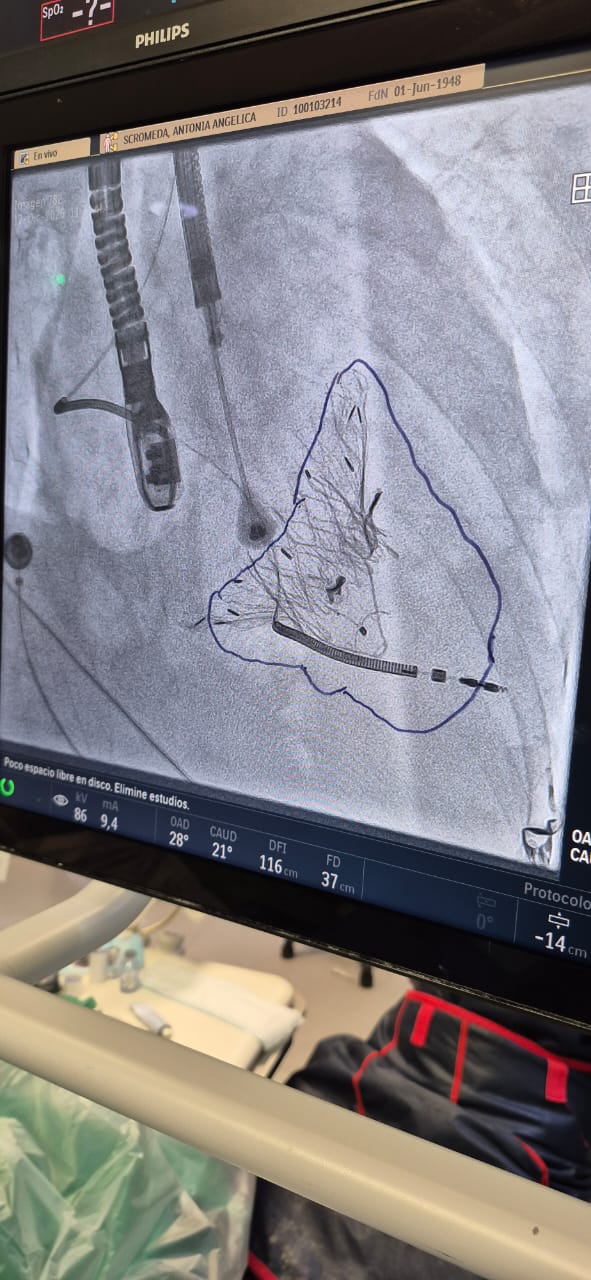

En el sanatorio Boratti se llevó a cabo el primer implante en la provincia y las primeras válvulas de este tipo que se colocan en Argentina para la insuficiencia tricúspide. En la misma posición de la válvula que está enferma se coloca una nueva y se hace con una intervención mínimamente invasiva guiada por eco transesofágico bajo anestesia general.

La Lux Valve es una prótesis autoexpandible que se ancla directamente al anillo valvular y al septum (tabique que divide el corazón), lo que le da una estabilidad excepcional, incluso en anatomías muy dilatadas, algo habitual en la insuficiencia tricuspídea avanzada.

Se introduce vía transvenosa – Yugular y una vez dentro del corazón, la nueva válvula reemplaza por completo a la nativa enferma, restableciendo el flujo normal.